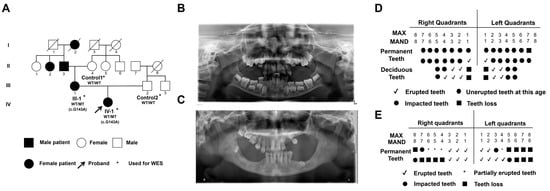

2.1. Clinical Characteristics of Primary Failure of Eruption (PFE) Individuals

| Patient | Sex (F/M) | Clinical Feature of PFE | Mutation | |||

|---|---|---|---|---|---|---|

| Nucleotide | Codon | Type | Location | |||

| I-2,II-2 | F | Doubtful | Unknown | Unknown | Unknown | Unknown |

| II-3 | M | Doubtful | Unknown | Unknown | Unknown | Unknown |

| III-1 | F | Yes | 143G > A | S48L | Missense | Extra-membrane |

| IV-1 | F | Yes | 143G > A | S48L | Missense | Extra-membrane |

| Control 1 | F | No | Wild-type | Normal | Normal | Extra-membrane |

| Control 2 | M | No | Wild-type | Normal | Normal | Extra-membrane |